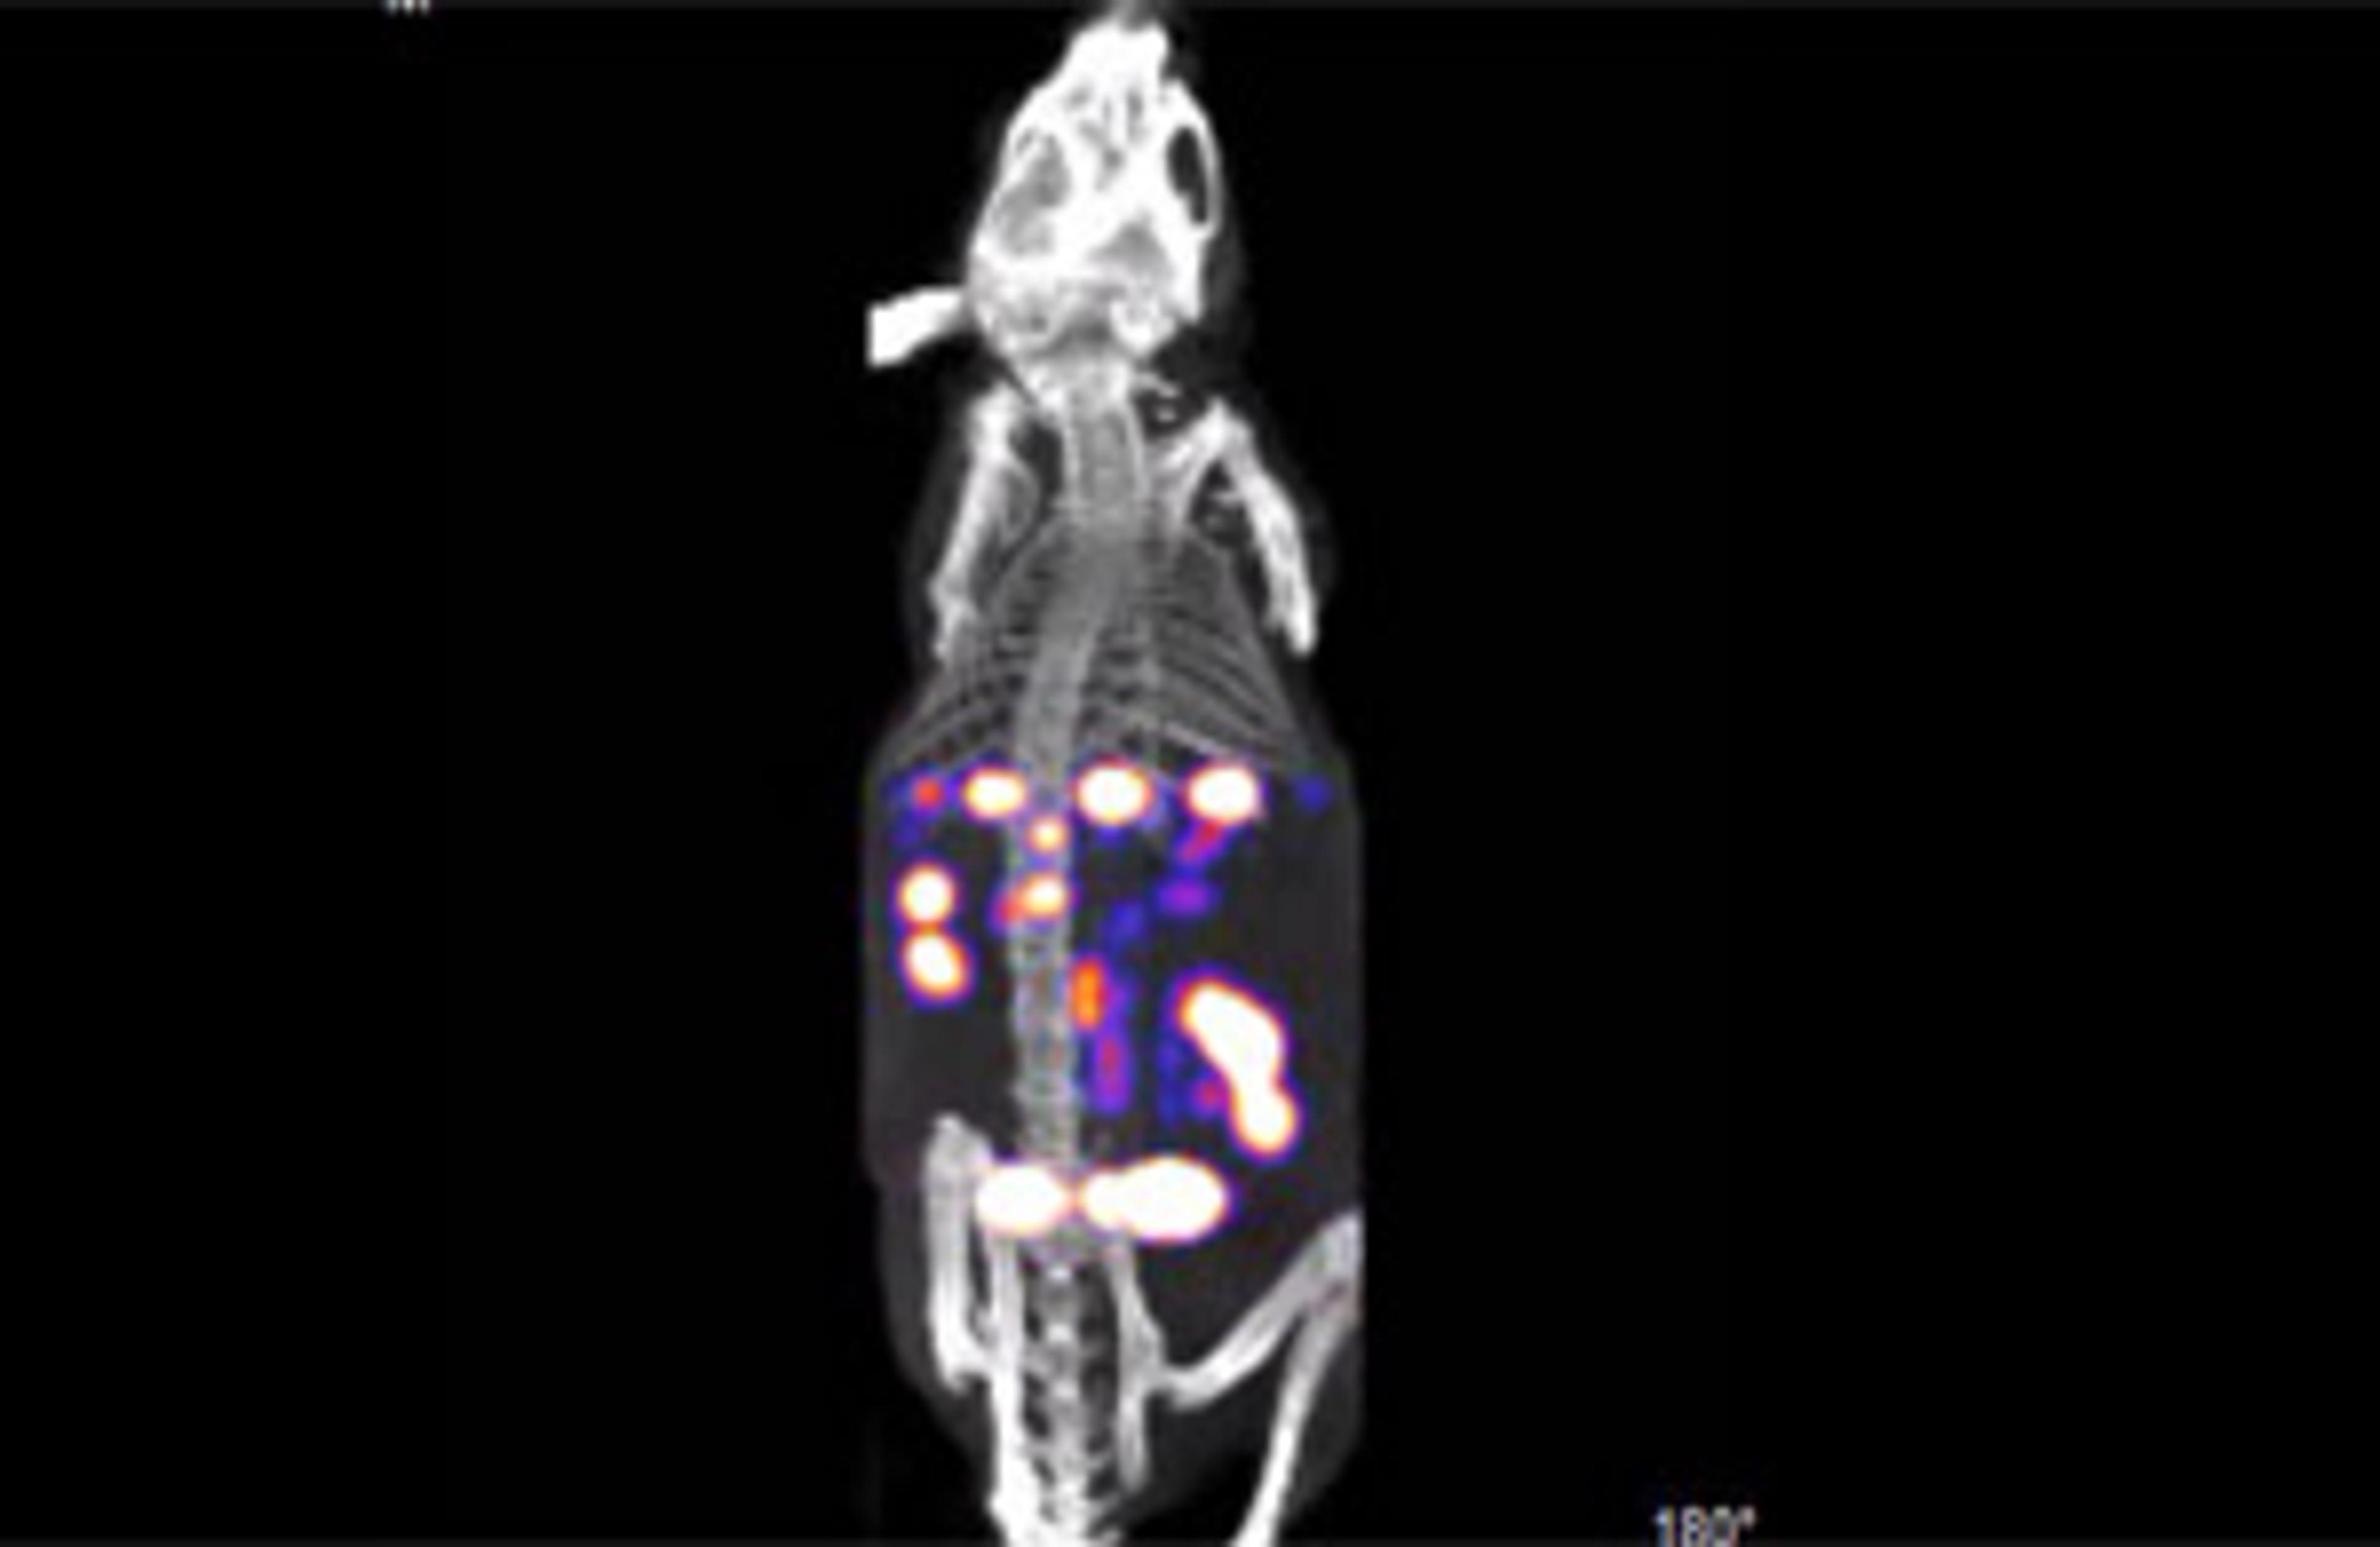

BioFLECT™ In Vivo Preclinical Imager

Watch this video to see the results that can be obtained using the BioFLECT™ In Vivo Preclinical Imager from Bioscan